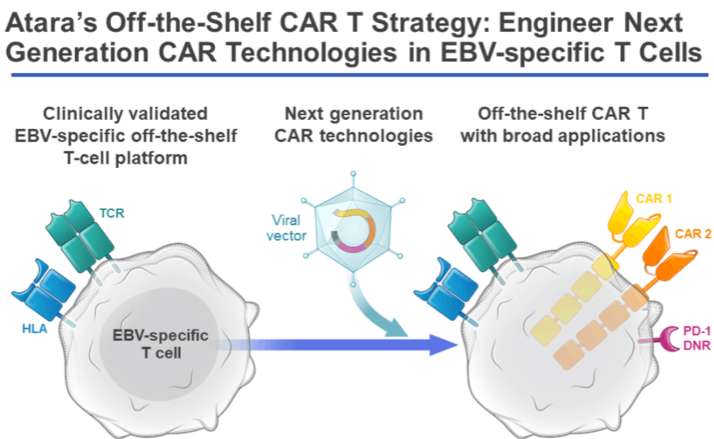

A pioneer in the T-cell immunotherapy space, Atara offers rapid delivery of Off-the-shelf bioengineered allogeneic T cells from donors with healthy immune function for the treatment of cancer, autoimmune and viral diseases. These can target cancerous and disease-causing cells with precision and eliminate them with minimal collateral cell damage. Most importantly, there is no need for lymphodepletion before treatment.

The company is leveraging its decade long clinical experience at Memorial Sloan Kettering (MSK) by using cell selection algorithm to identify the most appropriate T-Cell lines by matching key immune characteristics.

Its lead product candidate for mesothelioma is ATA2271 that uses a novel CAR T 1XX co-stimulation and CAR T PD-1 DNR, which is in preclinical stage. A MSK sponsored Phase 1 study (NCT02414269) of a mesothelin-targeted CAR T immunotherapy is currently under progress with emphasis on development of a next-generation, mesothelin-targeted CAR T using novel 1XX CAR signaling and PD-1 dominant negative receptor (DNR) checkpoint inhibition technologies. The company has exclusive licensed global rights to a mesothelin-targeted chimeric antigen receptor T-cell (CAR T) immunotherapy for solid tumors from Memorial Sloan Kettering Cancer Center (MSK) as per a company press release.

Image Source: https://www.atarabio.com/science-and-technology/next-generation-car-t-technologies/

The company is fully focused on CAR T opportunities and is developing numerous next generation and off-shelf technology options that cover a gamut of targets and diseases, overcome resistance and have an improved safety profiles. It has collaboration with Moffitt Cancer Centre and MSK to develop multi-targeted CAR T Immunotherapies.